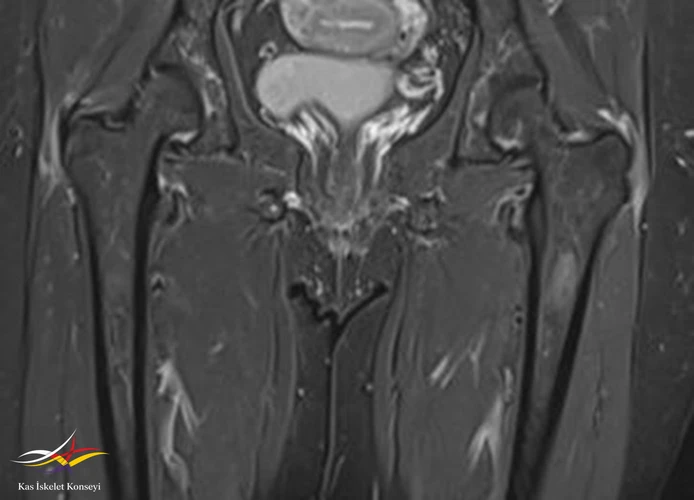

İncelemeler: Lomber MRG: L4-5 diskal bulging ve sol foraminal stenoz var. Kalça MRG istendi, iki yanlı trokanterik bursit rapor edildi.